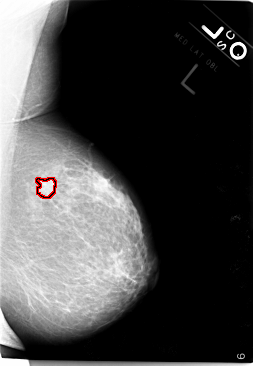

B_3017_1.LEFT_CC

LEFT_CC LINES 5888 PIXELS_PER_LINE 4056 BITS_PER_PIXEL 12 RESOLUTION 50 OVERLAY

FILE: B_3017_1.LEFT_CC.OVERLAY

TOTAL_ABNORMALITIES 1

ABNORMALITY 1

LESION_TYPE MASS SHAPE LOBULATED-ARCHITECTURAL_DISTORTION MARGINS MICROLOBULATED-SPICULATED

ASSESSMENT 4

SUBTLETY 5

PATHOLOGY MALIGNANT

TOTAL_OUTLINES 1

BOUNDARY